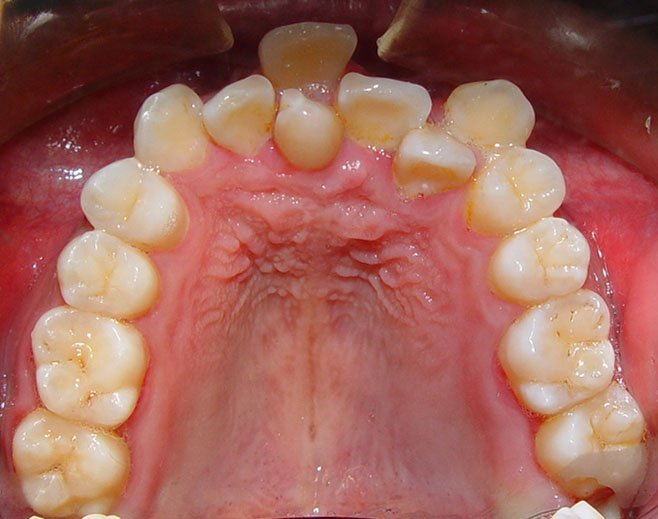

阻断性矫治除及时消除病因外,还要及时中断已经发现或正在发育中的畸形,重建正常合。包括缩小了的间隙再获得,阻断因牙数目、牙大小、唇系带异常及不良习惯等引起的错合或正在形成的错合。

(1)多生牙的拔除